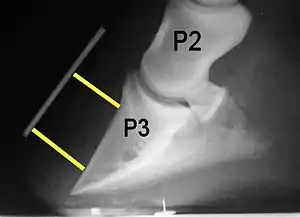

Rotation, sinking, and founder

Normally, the front of the third phalanx is parallel to the hoof wall and its lower surface should be roughly parallel to the ground surface. A single severe laminitic episode or repeated, less severe episodes can, depending upon the degree of separation of dermal and epidermal laminae, lead to either rotation or sinking of the pedal bone, both of which result in anatomical changes in the position of the coffin bone with visible separation of the laminae, colloquially known as founder. Rotation and distal displacement may occur in the same horse.[4] Both forms of displacement may lead to the coffin bone penetrating the sole. Penetration of the sole is not inherently fatal; many horses have been returned to service by aggressive treatment by a veterinarian and farrier, but the treatment is time-consuming, difficult and expensive.

Rotation is the most common form of displacement, and, in this case, the tip of the coffin bone rotates downward.[4] The degree of rotation may be influenced by the severity of the initial attack and the time of initiation and aggressiveness of treatment. A combination of forces (e.g. the tension of the deep digital flexor tendon and the weight of the horse) result in the deep digital flexor tendon literally pulling the dorsal face of the coffin bone away from the inside of the hoof wall, which allows the coffin bone to rotate. Also, ligaments attaching the collateral cartilages to the digit, primarily in the palmar portion of the foot, possibly contribute to a difference in support from front to back. The body weight of the animal probably contributes to rotation of the coffin bone. Rotation results in an obvious misalignment between PII (the short pastern bone) and PIII (the coffin bone). If rotation of the third phalanx continues, its tip can eventually penetrate the sole of the foot.

Radiographs

Radiographs are an important part of evaluating the laminitic horse. They not only allow the practitioner to determine the severity of the episode, which does not always correlate with degree of pain,[1] but also to gauge improvement and response to treatment. Several measurements are made to predict severity. Additionally, radiographs also allow the visualization and evaluation of the hoof capsule, and can help detect the presence of a lamellar wedge or seromas.[1] The lateral view provides the majority of the information regarding degree of rotation, sole depth, dorsal hoof wall thickness, and vertical deviation.[1][17] A 65-degree dorsopalmar view is useful in the case of chronic laminitis to evaluate the rim of the coffin bone for pathology.[1]

- Radiographic measurements

Several radiographic measurements, made on the lateral view, allow for objective evaluation of the episode.

- Coronary extensor distance (CE): the vertical distance from the level of the proximal coronary band to the extensor process of P3. It is often used to compare progression of the disease over time, rather than as a stand-alone value. A rapidly increasing CE value can indicate distal displacement (sinking) of the coffin bone, while a more gradual increase in CE can occur with foot collapse. Normal values range from 0–30 mm, with most horses >12–15 mm.[1]

- Sole depth (SD): the distance from the tip of P3 to the ground.

- Digital breakover (DB): distance from the tip of P3 to the breakover of the hoof (dorsal toe).[1]

- Palmar angle (PA): the angle between a line perpendicular to the ground, and a line at the angle of the palmar surface of P3.

- Horn:lamellar distance (HL): the measurement from the most superficial aspect of the dorsal hoof wall to the face of P3. 2 distances are compared: a proximal measurement made just distal to the extensor process of P3, and a distal measurement made toward the tip of P3. These two values should be similar. In cases of rotation, the distal measurement will be higher than the proximal. In cases of distal displacement, both values will increase, but may remain equal. Therefore, it is ideal to have baseline radiographs for horses, especially for those at high-risk for laminitis, to compare to should laminitis ever be suspected. Normal HL values vary by breed and age:[1]

Several radiographic abnormalities can be judged to correlate with a worsened prognosis:

- Increased degree of rotation of P3 relative to the dorsal hoof wall (rotation greater than 11.5 degrees has a poorer prognosis)[4]

- Increased founder distance, the vertical distance from the coronary band (seen with a radio-opaque marker) to the dorsoproximal aspect of P3 (distance greater than 15.2mm has a poorer prognosis)[4]

- Decreased sole depth[4]

- Sole penetration by P3